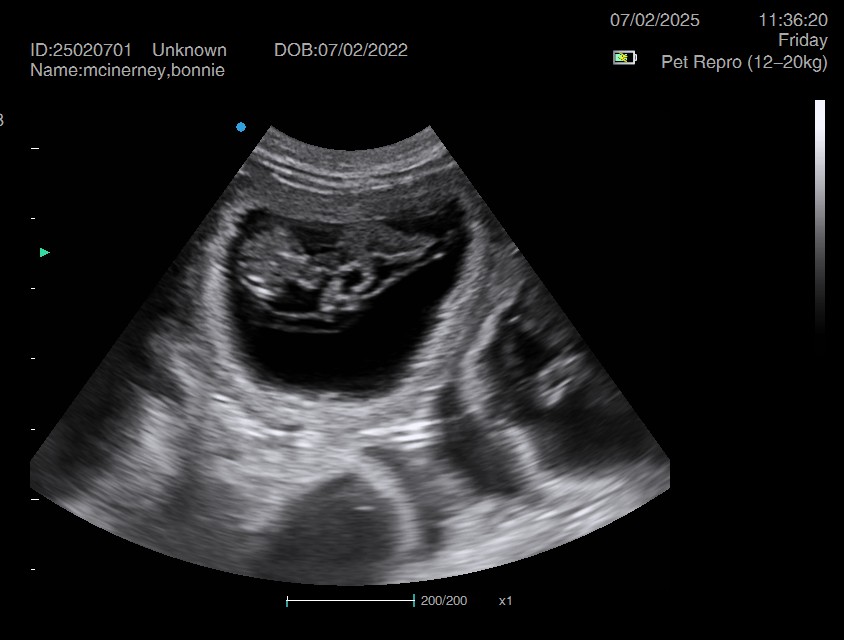

Ultrasound pregnancy scanning is a safe, non-invasive way to confirm pregnancy in dogs and cats, offering breeders and pet owners peace of mind and vital information to support responsible care. It allows us to detect gestational sacs, assess foetal development, and estimate litter size—all while ensuring the wellbeing of the animal.

Pregnancy can sometimes be detected as early as Day 18 post-mating, but scanning at this stage is not routinely recommended. Embryos are still developing and may not be clearly visible, and there is a natural risk of embryo resorption, which can lead to misleading or inconclusive results.

For the most accurate and reliable scan, we advise booking between Day 25 and Day 32, when pregnancy is more easily confirmed and foetal structures are clearer. If an early scan is performed and no pregnancy is detected, we offer a FREE complimentary re-scan after 7 days at the clinic to ensure clarity and support informed decision-making.

Our approach balances early insight with ethical care—always prioritizing the comfort of the animal and the accuracy of the results.